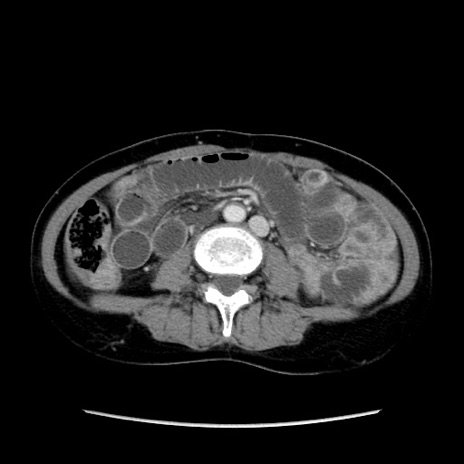

矢状断像